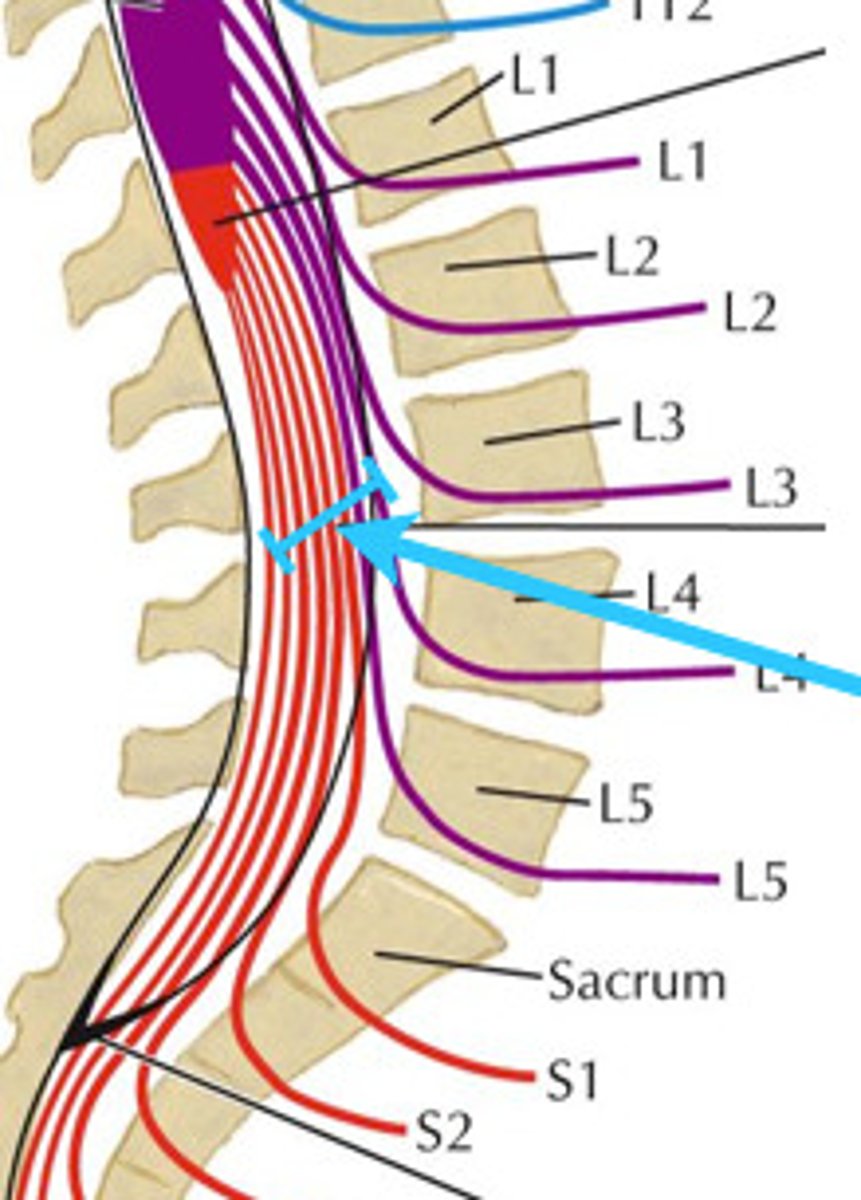

conus medullaris

L1/L2

what level is the conus medullaris located

what level does spinal cord end

condus medullaris

what is the name of where the spinal cord ends

cauda equina

condus medullaris

L1-L2

what vertebra is the condus medullarius located